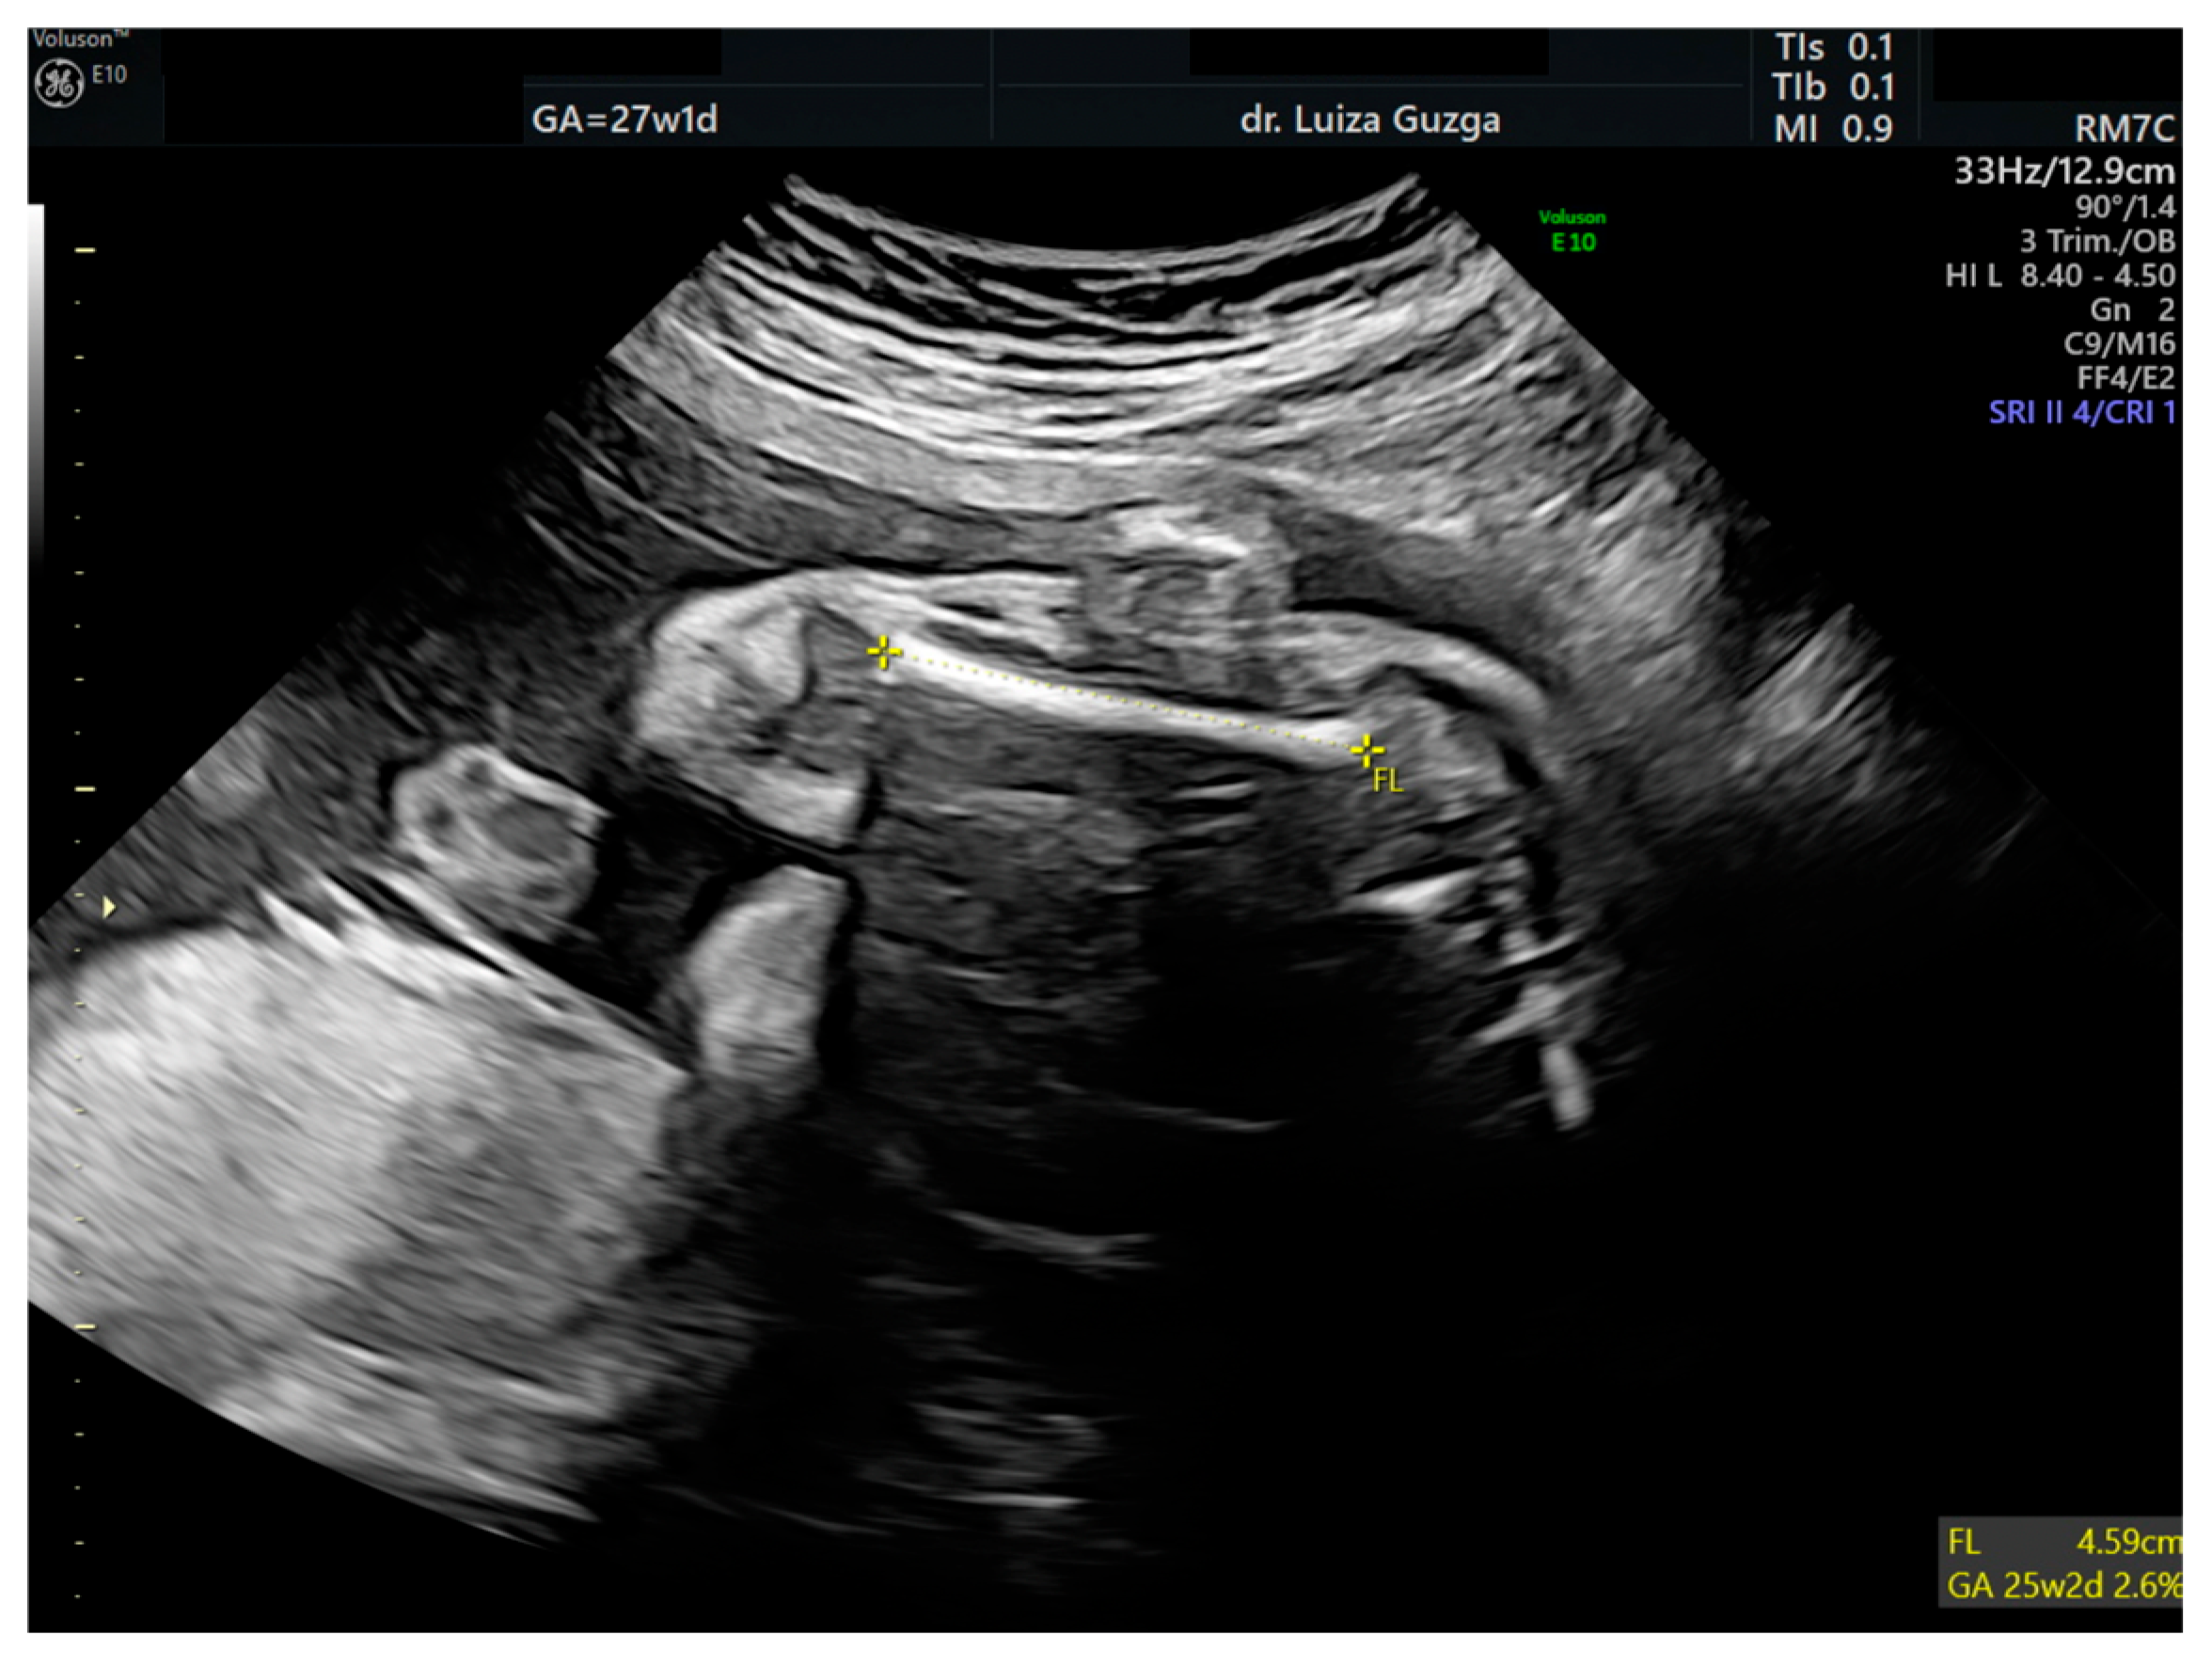

| Short femur | - | + | ++ | +++ |

| Short long bones | x | x | |||||||||||||